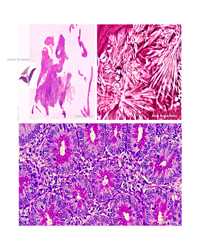

II. International PathArt Photomicrography Contest

In doing so, we want to use art and its beautiful and positive influences on human soul as a way to express ourselves. In this context, we want to share our world, our imagination from the colors of our world and its reflections on reality with the abstractions coming out of our microcopes that we spend most of our days with.